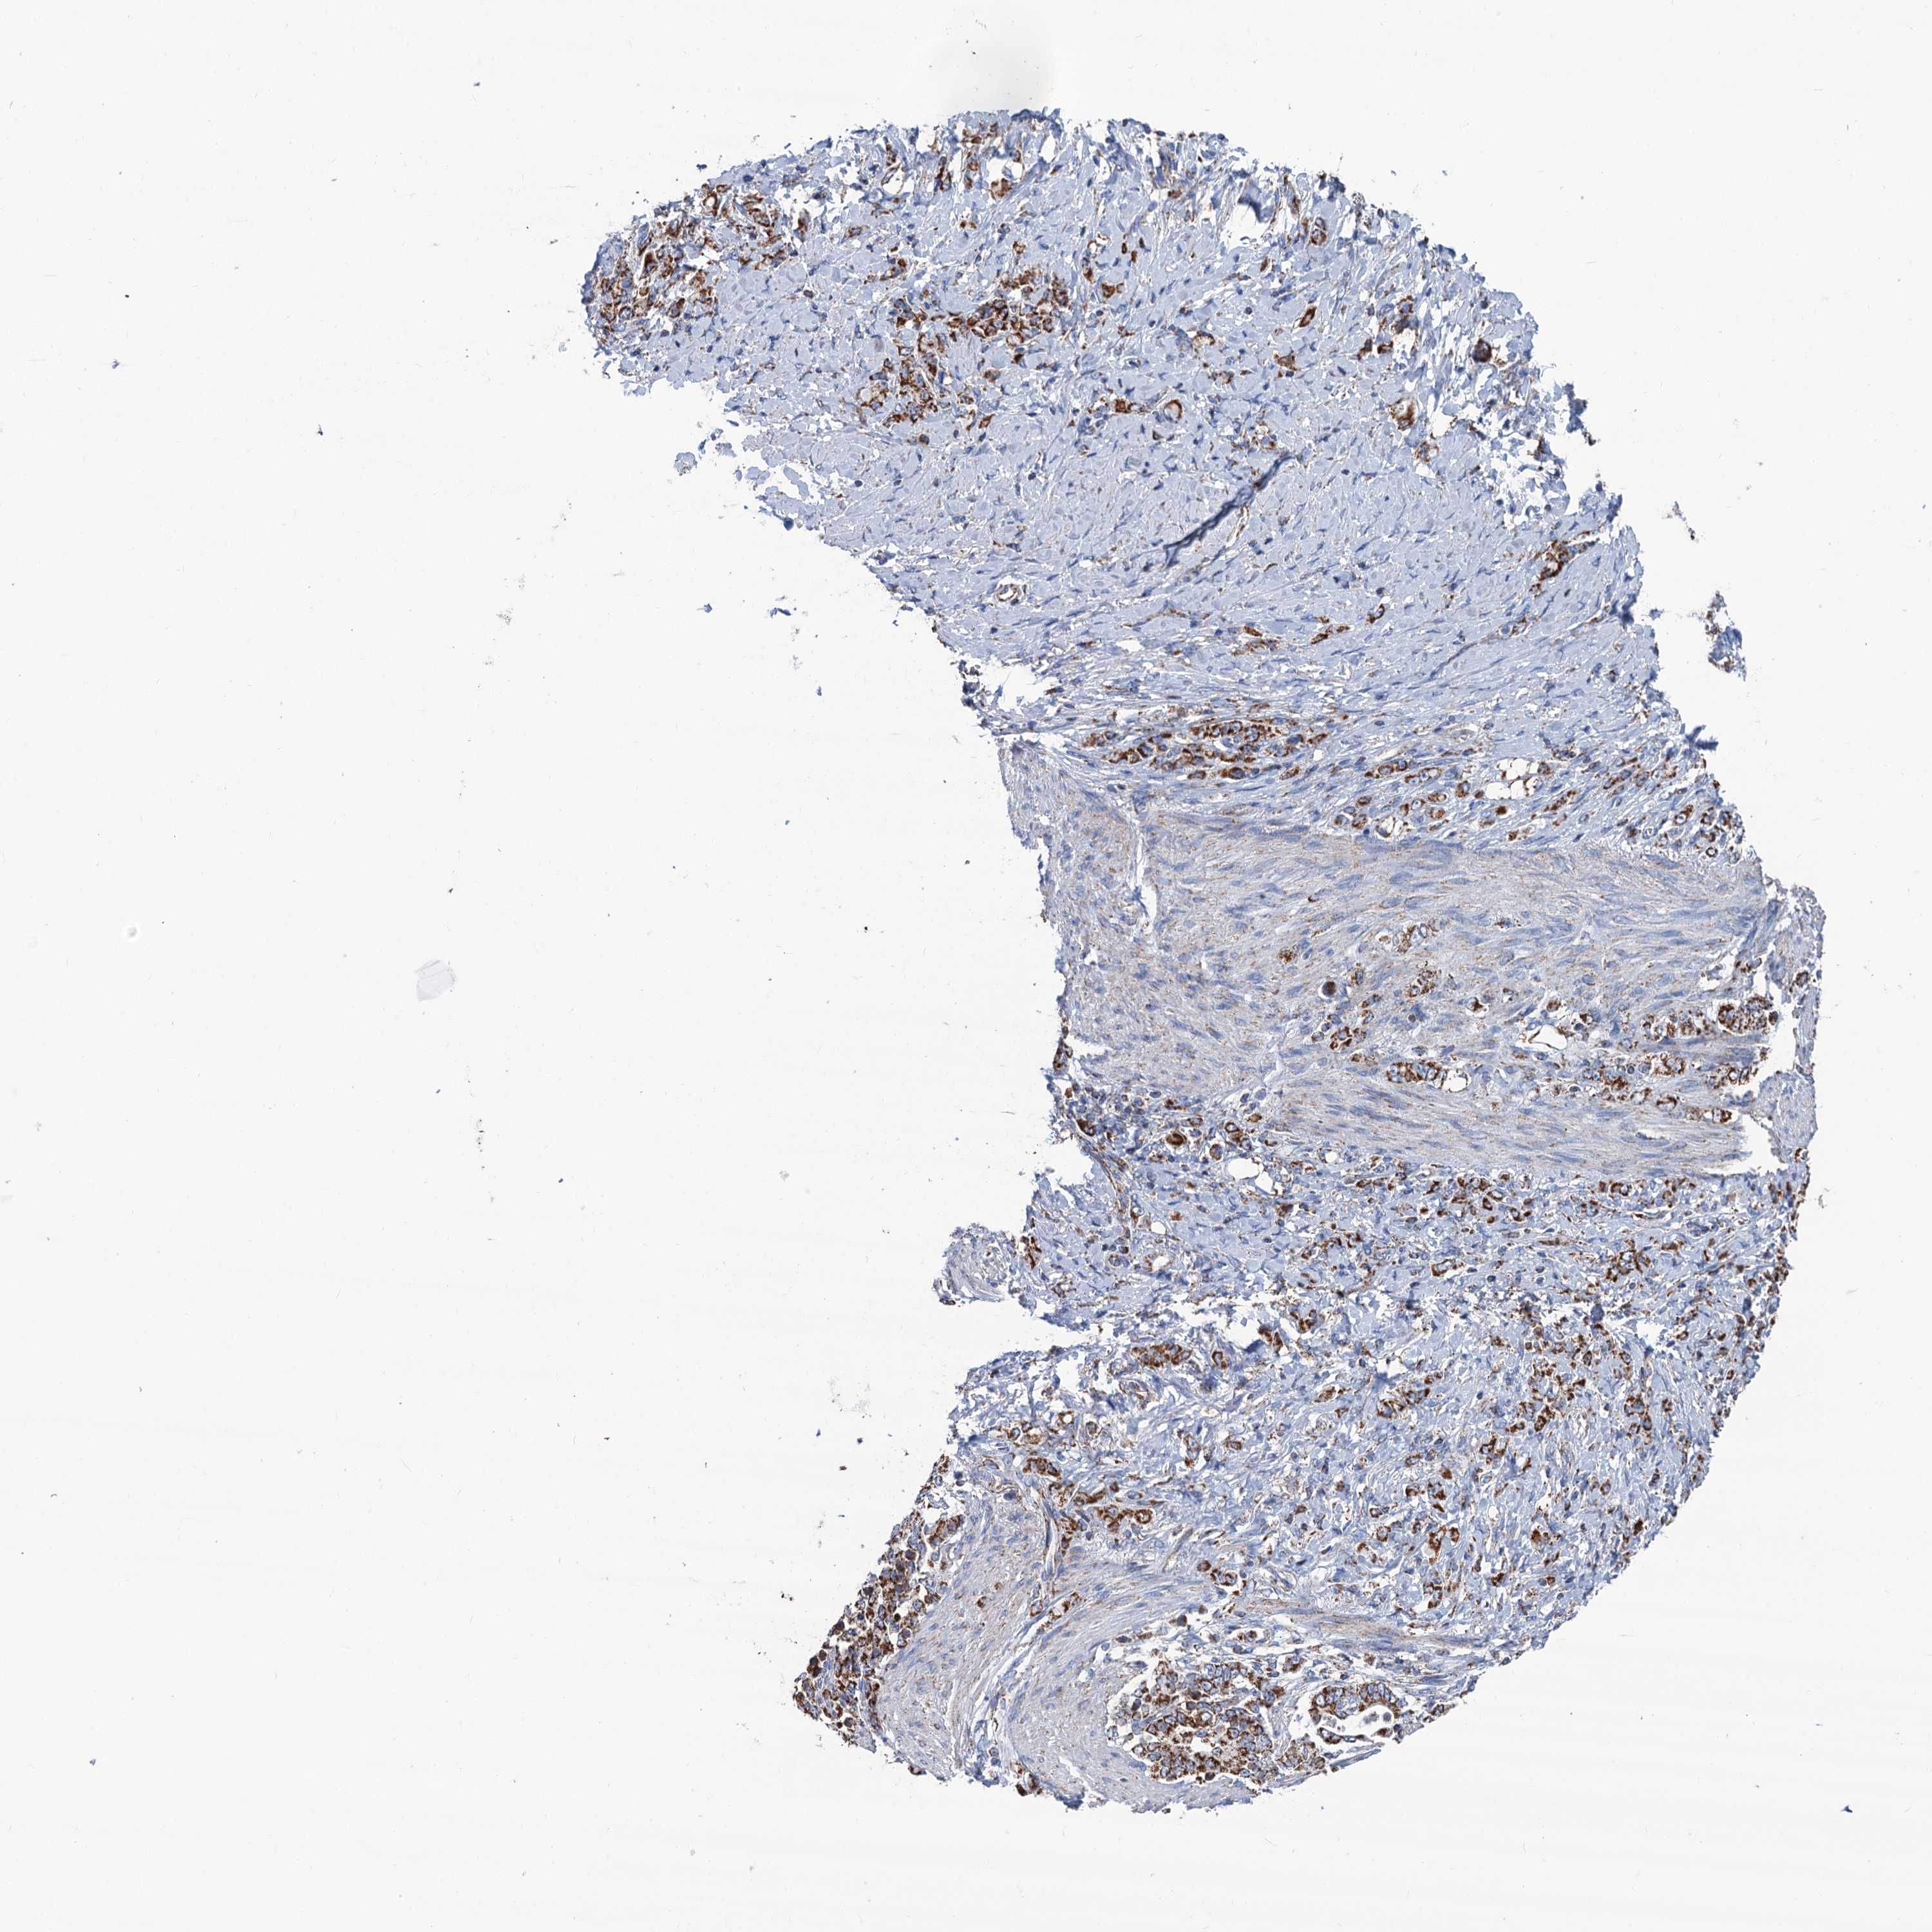

STOMACH CANCER - Protein expressioni

A mouse-over function shows sample information and annotation data. Click on an image to view it in a full screen mode. Samples can be filtered based on level of antibody staining by selecting one or several of the following categories: high, medium, low and not detected. The assay and annotation is described here.

Note that samples used for immunohistochemistry by the Human Protein Atlas do not correspond to samples in the TCGA dataset.

Antibody stainingi

Antibody staining in the annotated cell types in the current human tissue is reported as not detected, low, medium, or high, based on conventional immunohistochemistry profiling in selected tissues. This score is based on the combination of the staining intensity and fraction of stained cells.

Each image is clickable and will lead to virtual microscopy that enables deeper exploration of all samples and also displays staining intensity scores, fraction scores and subcellular localization as well as patient and tissue information for each sample.

Antibody HPA041391

Antibody HPA044250

Staining

High

Medium

Low

Not detected

Intensity

Strong

Moderate

Weak

Negative

Quantity

>75%

75%-25%

<25%

None

Location

Nuclear

Cytoplasmic/membranous

Cytoplasmic/membranous,nuclear

Adenocarcinoma, NOS

Adenocarcinoma, High grade